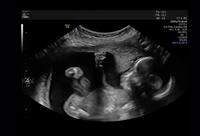

VÍDEO: ultrassom flagra bebê 'dando soco' na mãe e cena viraliza

Vídeo gravado em consultório mostra momento inusitado na 20ª semana de gravidez; mãe brinca que filha pode ser a próxima Ronda Rousey

Um exame de rotina acabou se transformando em um momento divertido em um consultório médico no estado de Michigan, nos Estados Unidos. Durante a ultrassonografia feita em setembro, quando estava na 20ª semana de gestação, Mara McCoy foi surpreendida pela filha, Pyper, que apareceu nas imagens parecendo “dar um soco” na barriga da mãe.

A cena, registrada em vídeo pelo pai, Terrance McCoy, chamou a atenção da equipe médica, que caiu na gargalhada ao ver o gesto da bebê. O vídeo acabou viralizando nas redes sociais e rendeu comentários bem-humorados de familiares e internautas.

Para Mara, o episódio mostra que a filha já demonstra traços de personalidade marcante. “O vídeo mostra o quão brava ela é”, disse, em entrevista à revista Newsweek. “Ela estava muito ativa e pareceu me dar um soco. Pode ser a próxima Ronda Rousey”, brincou, fazendo referência à lutadora de MMA.

O parto de Pyper está previsto para o dia 2 de fevereiro de 2026, o que fará dela uma aquariana. “Estou ansiosa para ver o seu lindo rostinho e conhecer a sua personalidade fofa”, comentou a mãe, que também fez questão de negar que o vídeo tenha sido gerado por inteligência artificial.

Segundo especialistas ouvidos pela Newsweek, movimentos como o de Pyper são completamente normais nessa fase da gestação. Chutes, socos e alongamentos indicam que o bebê está ativo e se desenvolvendo de forma saudável dentro do útero.